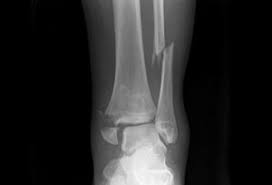

Fractures

are breaks or cracks in bones.

Pott’s

Colles’